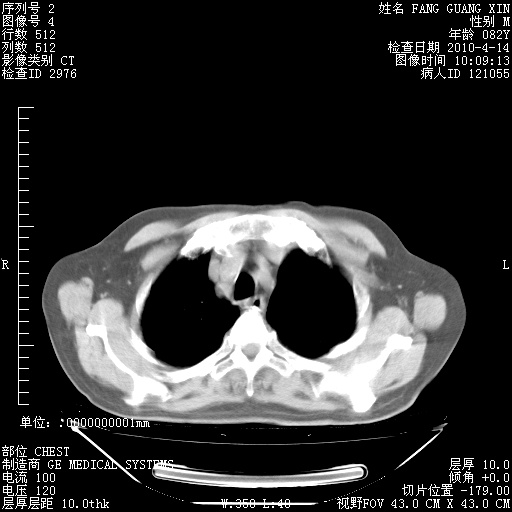

4月14日肺部CT

肺部CT平扫未见异常。